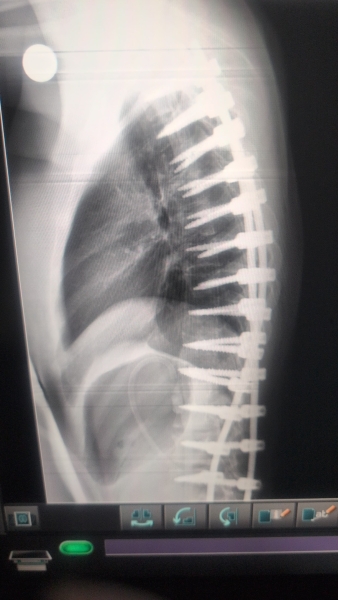

بتوجيهات معالي وزير الصحة إبراهيم البدور، ومتابعة مدير مستشفيات البشير الدكتور الإنسان علي العبدالات، نجح النِّطاسي المبدع الدكتور جاسر الزبيدي في تنفيذ عملية جراحية دقيقة ومعقّدة لإصلاح تشوّه في العمود الفقري لطفلة كانت تعاني من حالة صحية معقّدة.

وجاءت العملية الجراحية بعد تقييم طبي شامل ودقيق للحالة، حيث استخدم الفريق الجراحي أحدث التقنيات المتخصصة في جراحات العمود الفقري، ما أسهم في تصحيح التشوّه وتحسين الاستقرار الوظيفي، وسط متابعة حثيثة لمراحل ما قبل وما بعد الجراحة.

حيث كانت الطفلة تعاني منذ سنوات من تشوّه خلقي في العمود الفقري، الأمر الذي انعكس سلبًا على قدرتها على ممارسة حياتها اليومية بشكل طبيعي، وتسبب لها بآلام وتحديات صحية مستمرة، إلى أن تكللت الجهود الطبية بإجراء هذه العملية الجراحية الدقيقة التي أعادت لها الأمل بتحسّن نوعية حياتها.